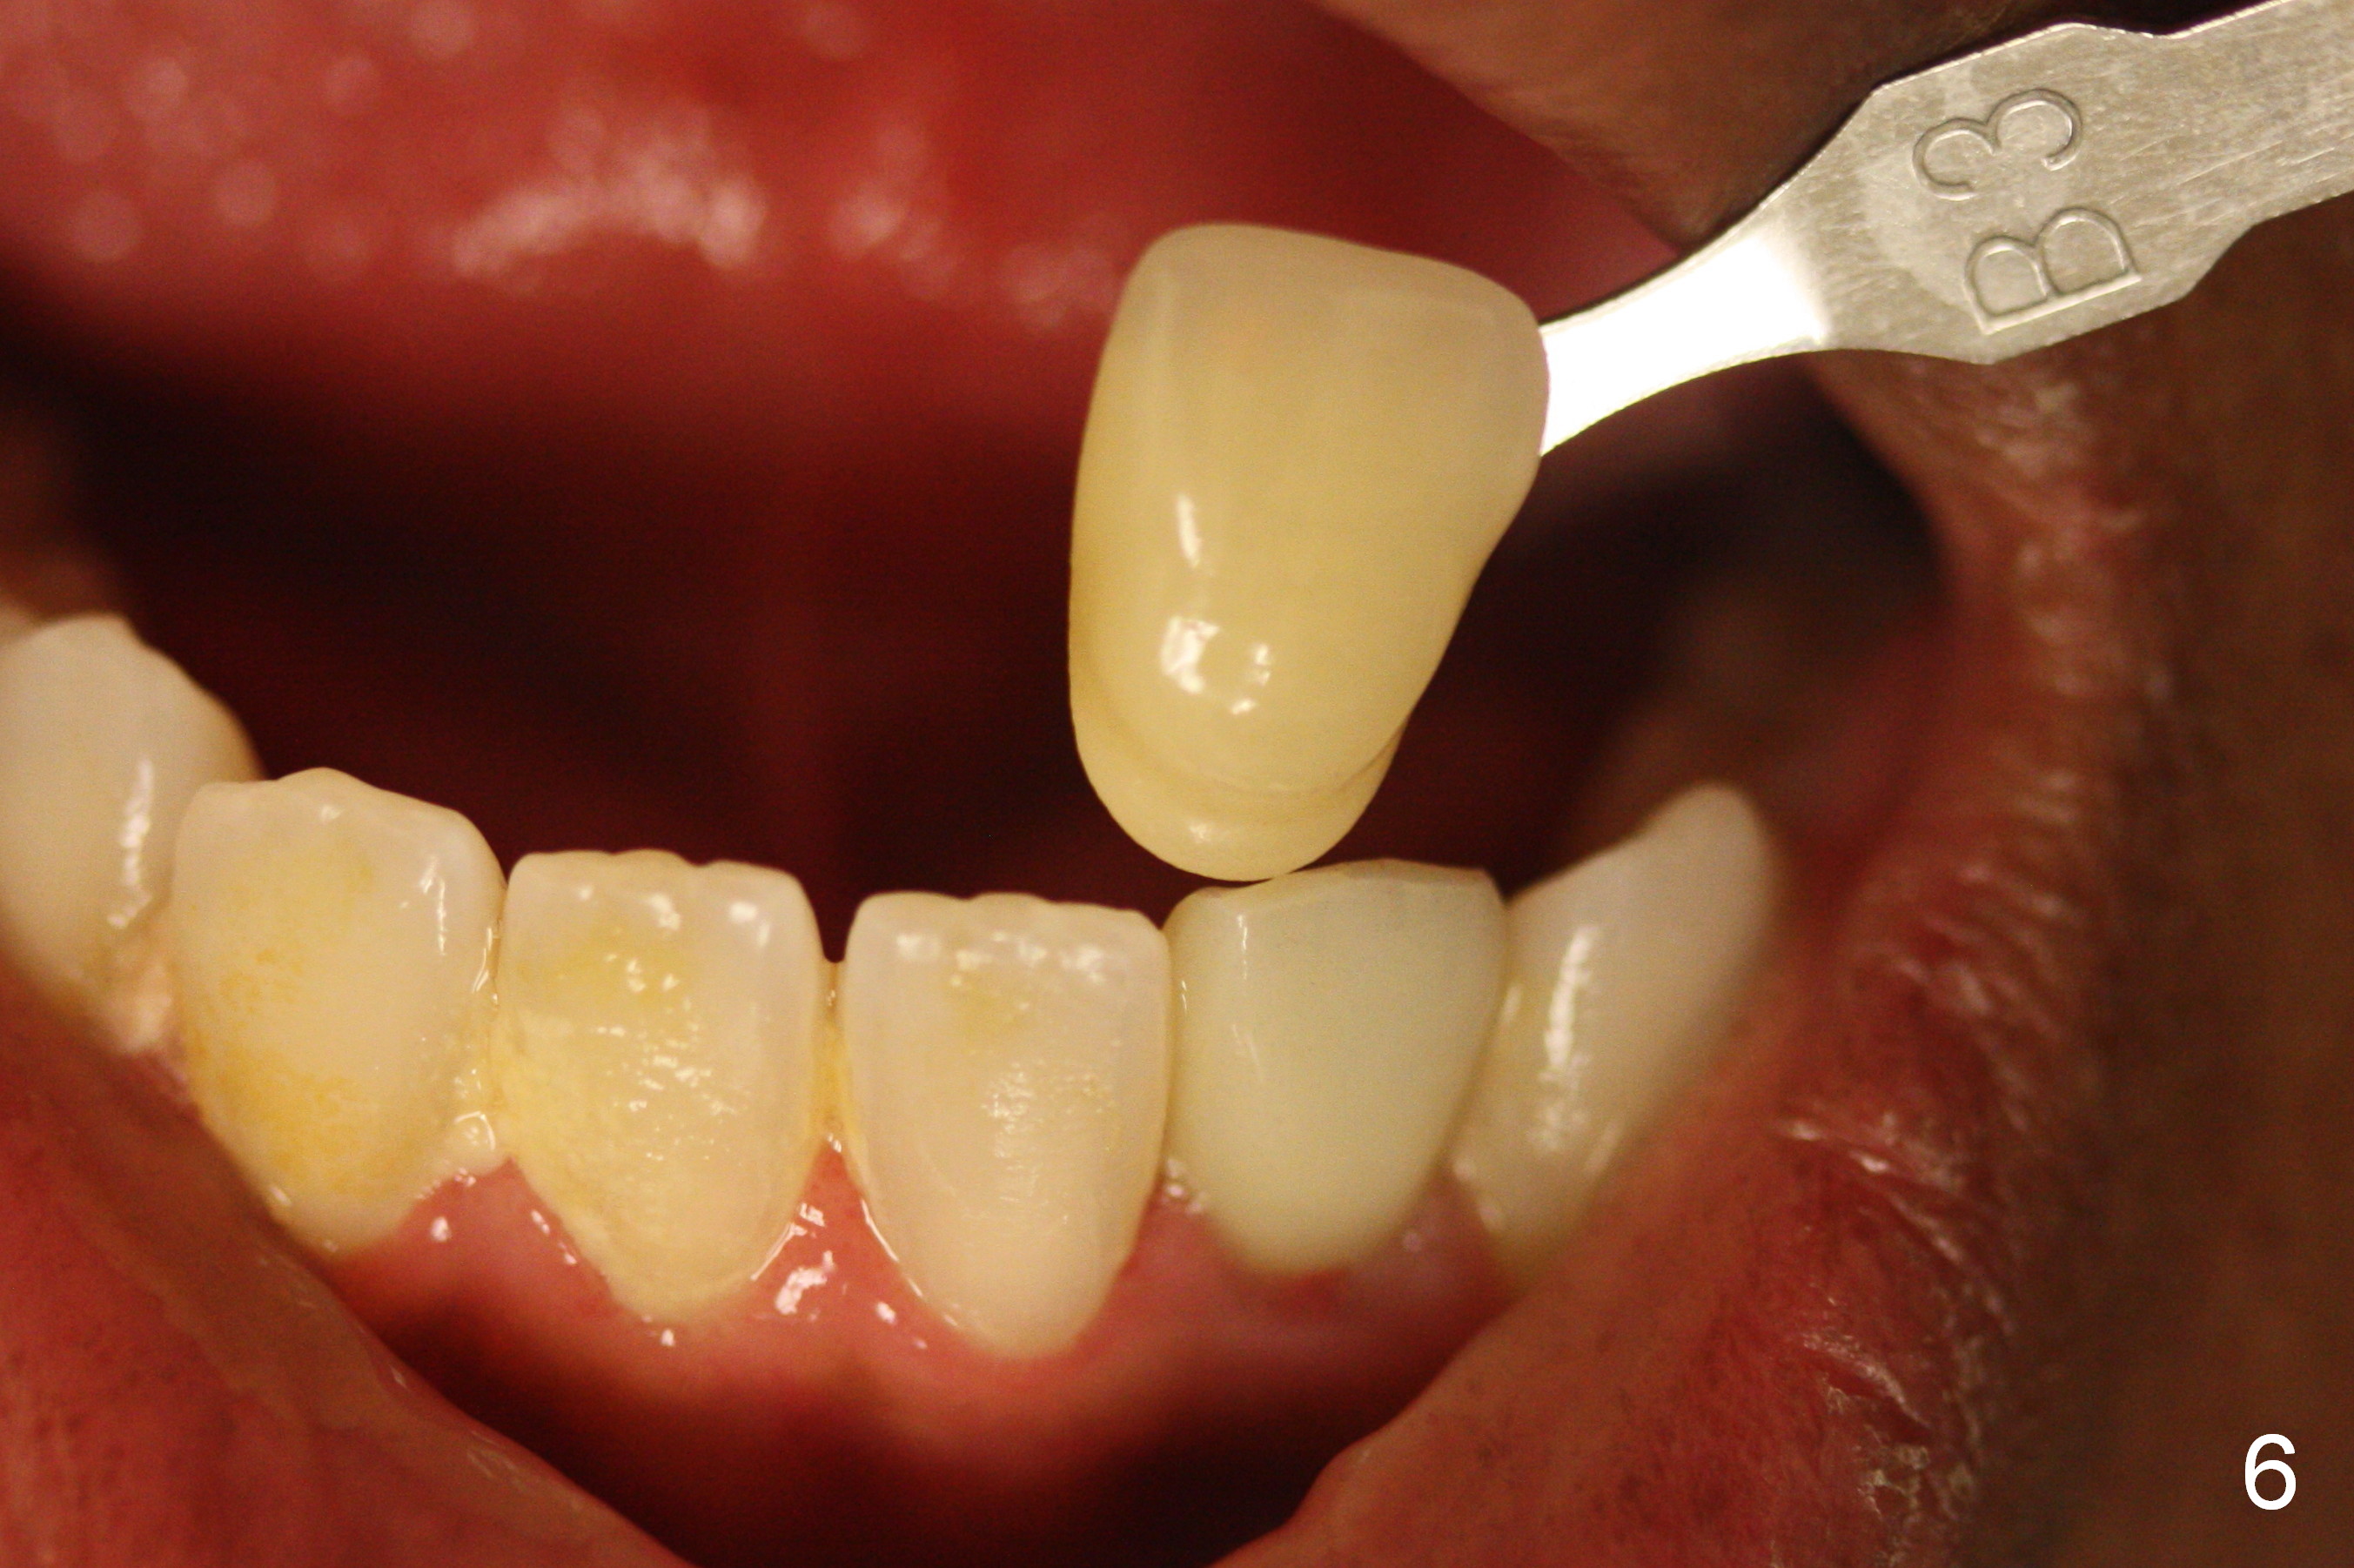

Suggestions for #23 implant crown redo (Fig.1, 2)

Make a new crown less transparent than the previous one (Fig.3). Can you block inside the crown to take care of the metal shade of the abutment/implant?

The original shade is A 2.5 (enclosed in the case).

Choose a shade a little darker and more yellowish (Fig.4-7 before

cleaning; Fig.9-11 after cleaning). It

appears that there is a change in shade of crown over the time.

Can you choose a Zirconia block that has the closest shade?

Do not stain or paint the crown.